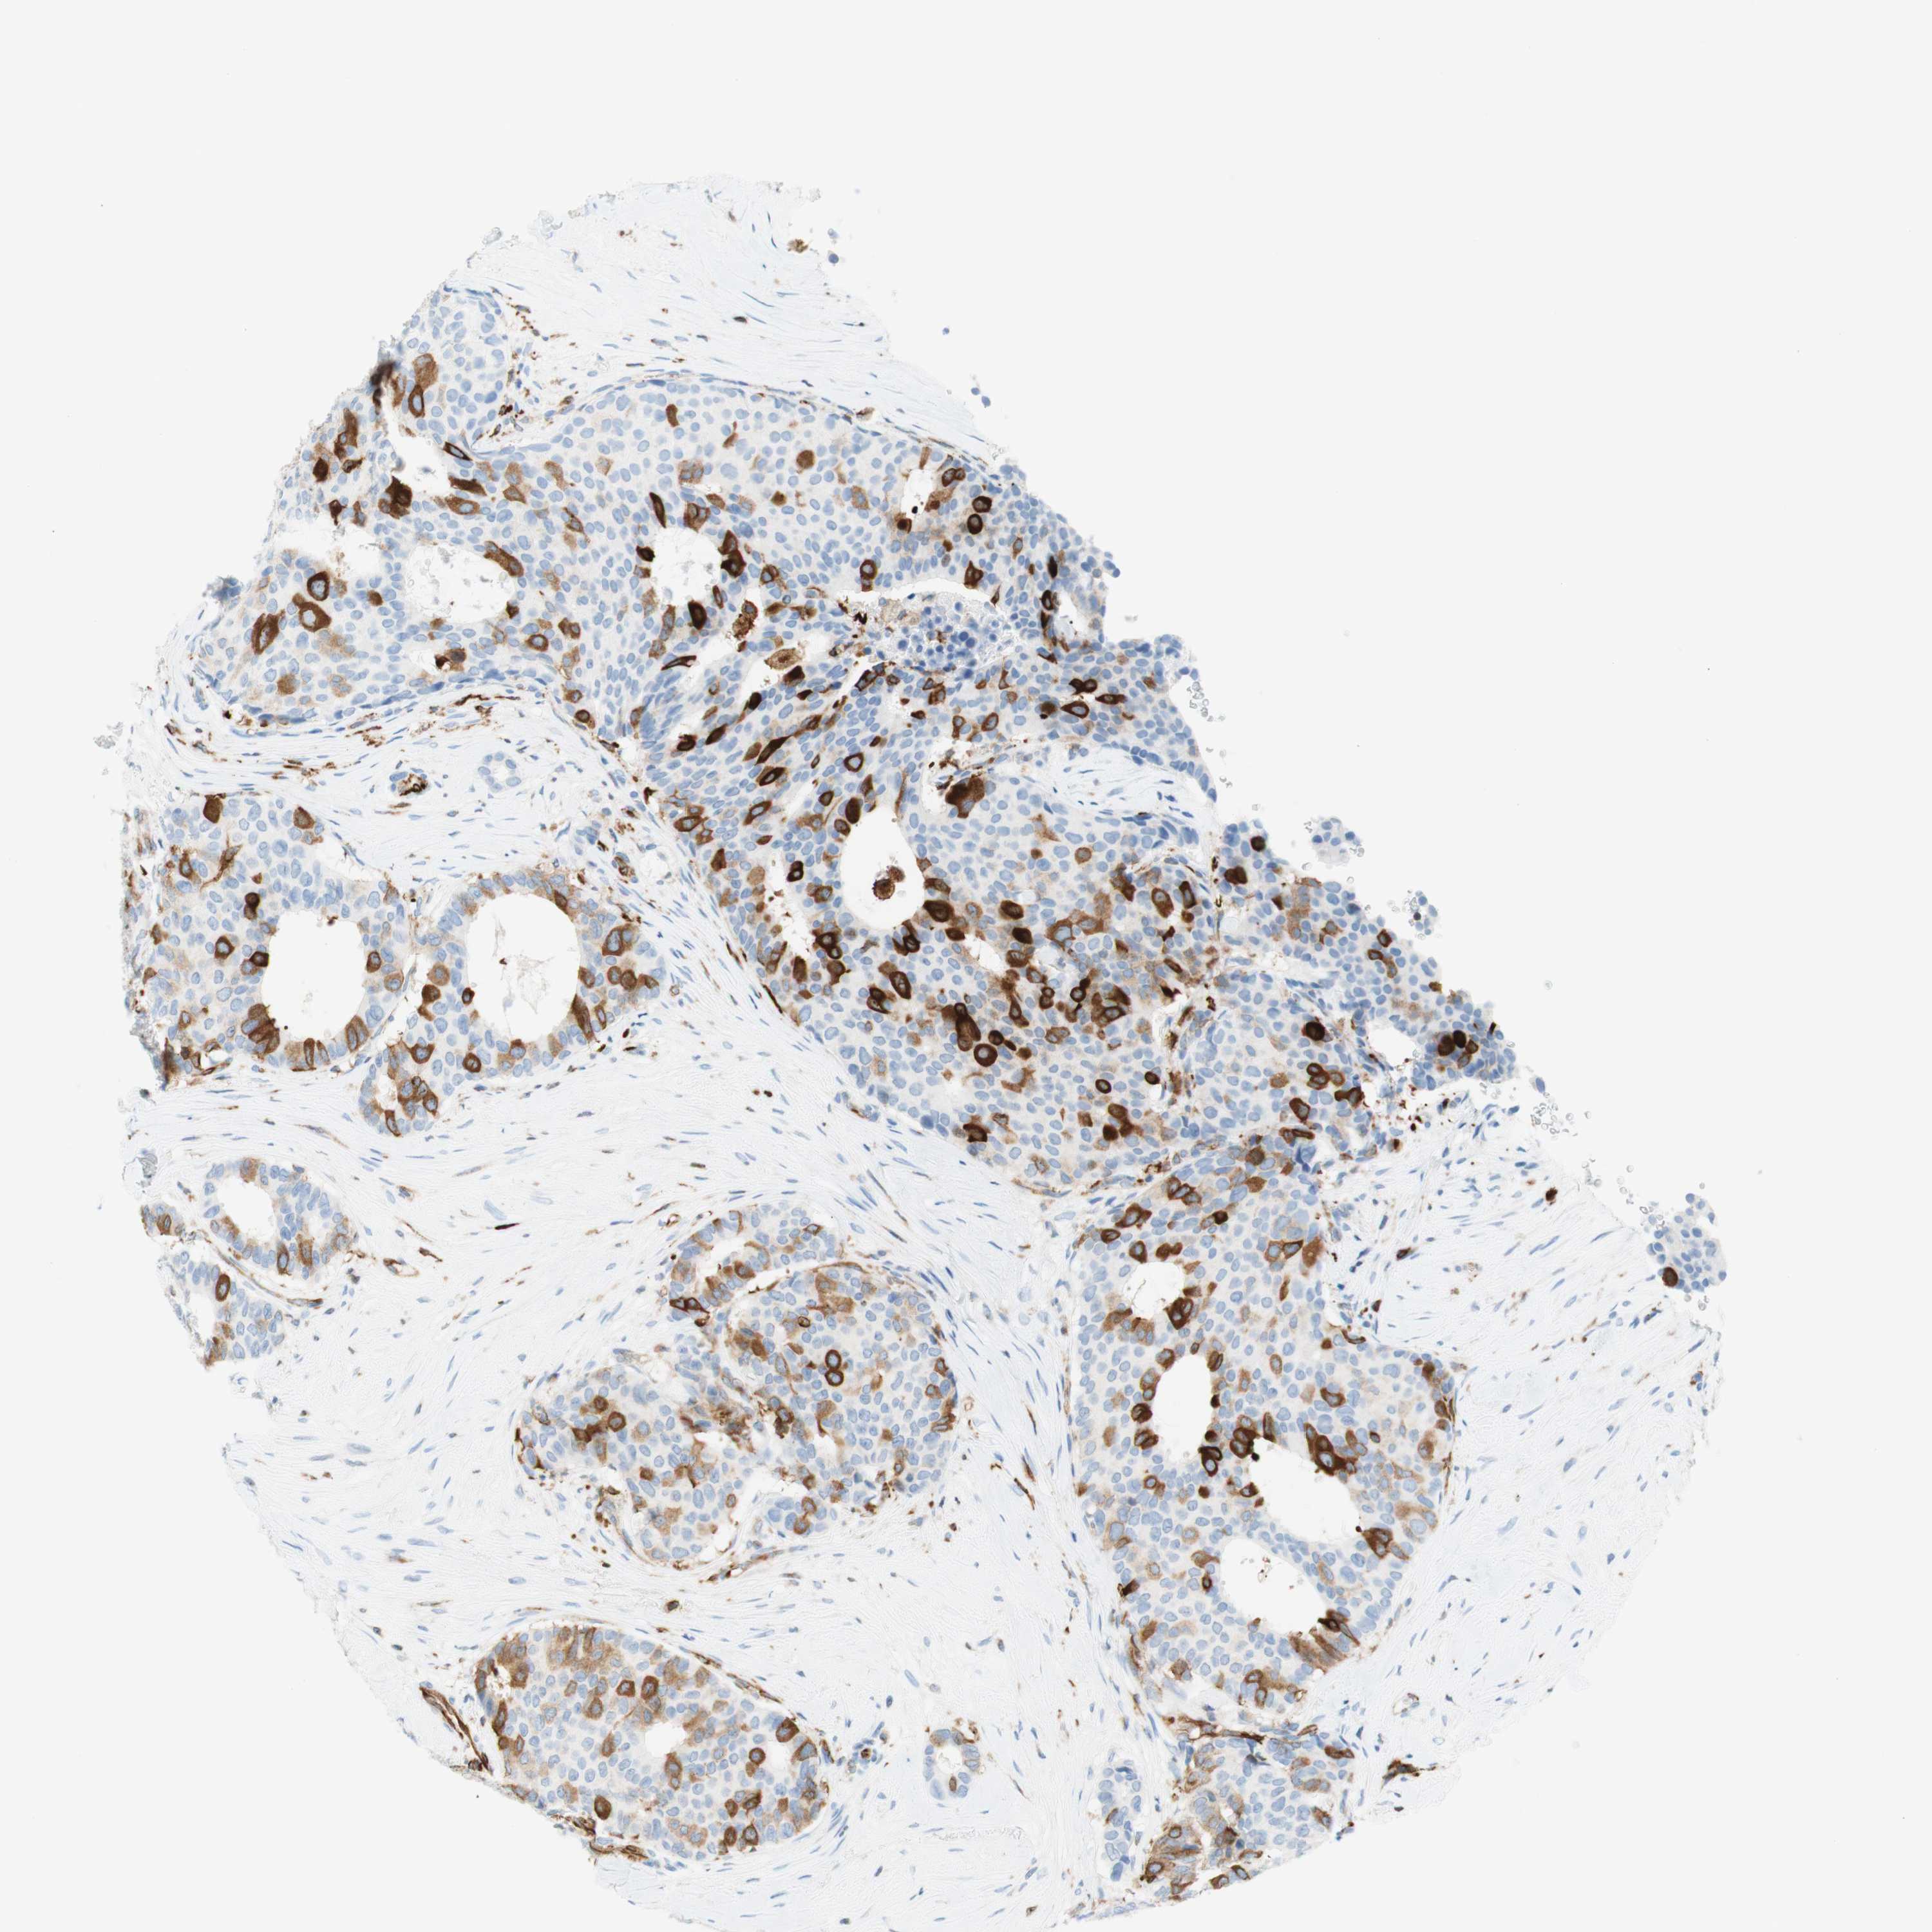

CANCER BREAST CANCER Show tissue menu

BRCA TCGA BRCA VALIDATION PROTEIN EXPRESSION